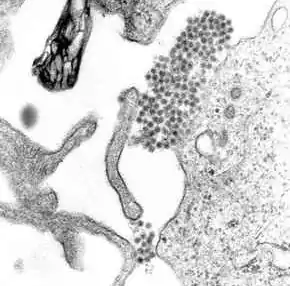

A transmission electron microscopy image showing dengue virus

A TEM micrograph showing dengue virus virions (the cluster of dark dots near the center)

Dengue fever virus (DENV) is an RNA virus of the family Flaviviridae; genus Flavivirus. Other members of the same genus include yellow fever virus, West Nile virus, Zika virus, St. Louis encephalitis virus, Japanese encephalitis virus, tick-borne encephalitis virus, Kyasanur forest disease virus, and Omsk hemorrhagic fever virus.[29] Most are transmitted by arthropods (mosquitos or ticks), and are therefore also referred to as arboviruses (arthropod-borne viruses).[29]